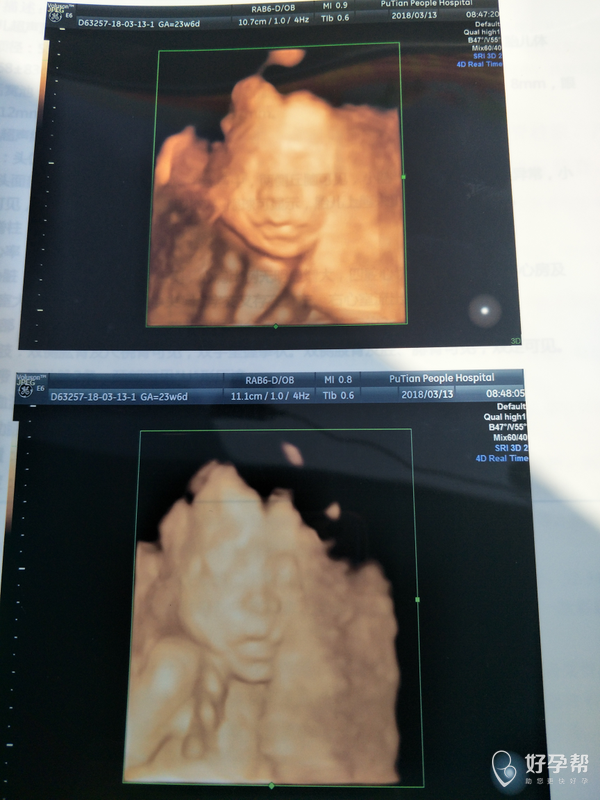

想看看是男孩女孩,方便买衣服

你好,四维报告是看不出来是男是女的。